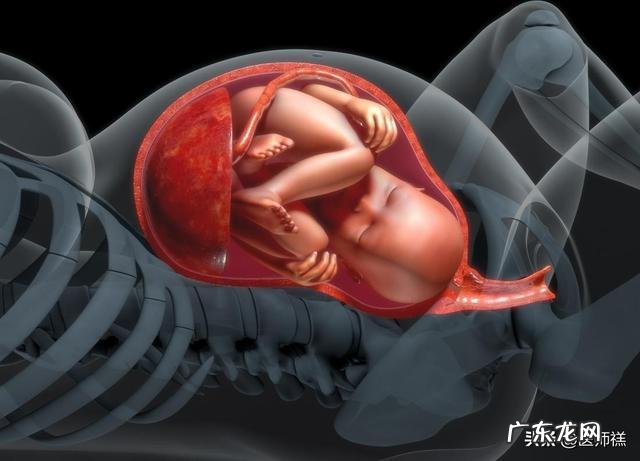

什么是胎儿头大胎儿头大通常存在一个判别的标准,随着胎儿的发育宝妈妈一般都会定期查体通过超声设备对宝宝头部的发育做一个基本的观察与了解以此判定胎儿的发育是否正常 。正常情况下孕周在12周胎儿的头围大约在56mm左右,发育至20周胎儿的头围一般在175mm左右,如果胎儿的头围远远超出限值和可能就是胎儿头部发育异常的现象 。但是我们的宝妈妈在孕检的过程中总会发现胎儿的头围超过正常的限值,很是担忧胎儿的发育是否异常 。其实胎儿头部过大也是存在正常生理改变以及异常病理变化的 。

正常生理改变胎儿正常发育:胎儿头部略微超过标准限值很可能是正常的发育改变 。孕妇的身体状态、在孕期摄入的营养状况均会使得胎儿的发育存在一些差异性的改变,营养状态供应足、母亲机体健康状况好有些胎儿的发育要确实要比营养供应不足的胎儿过快一些,如果在其他指标检测都正常的情况下这种现象其实不属于任何病症 。巨大胎儿:相反如果患儿营养供应过足在孕晚期胎儿的体重远远超过正常的4000g,这种营养过剩引起的胎儿发育状态我们也成为巨大胎儿 。巨大胎儿的发生通常是营养过度堆积引起,例如孕妇营养热量摄入过度引起机体过度的肥胖;妊娠过程中孕妇合并糖尿病,胎儿会吸收更多的能量导致体重异常发育过旺;除此以外对于高龄产妇、以及有巨大胎儿分娩史的产妇这种胎儿头大的现象也经常发生 。这种胎儿头大是属于胎儿正常发育范畴并不属于病理性的改变 。但是巨大胎儿常常会容易导致难产,特别是肩部难产很容易导致胎儿窒息死亡 。病理性胎儿头大胎儿脑积水:胎儿脑积水是由于胎儿脑脊液循环异常引发的一种疾病,引起疾病的因素有很多无论是先天性因素还是后天因素都会引起脑积水的发生 。例如下图A.注意手臂,前臂和手腕的长度明显减少 。